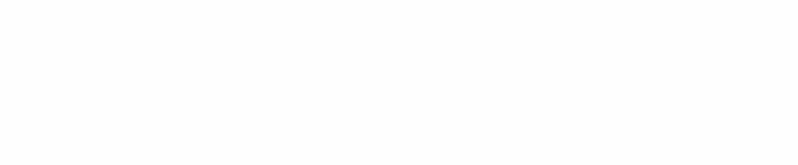

十月一日,河南郑州的一位13岁小女孩因为和父母闹矛盾,毒气喝下半瓶剧毒农药——百草枯。喝下之后,她并没有选择告诉父母,而是拍照发给了同学。

同学意识到事情的严重性连忙告诉了班主任,而后通知家长将女孩送进了医院。事情已经过去了挺长时间,据家人回应,刚开始的三天,女孩的状态很好,肾脏等器官也一切如常,直到第四天下午......

“她的肺只剩下一小块了”

“肺部一个小时一变,今天早上就只剩下一点点了”

面对镜头,女孩的家人忍不住转过头放声大哭,从确诊吞服百草枯,到接二连三的病危通知书,一切都发生得太快。